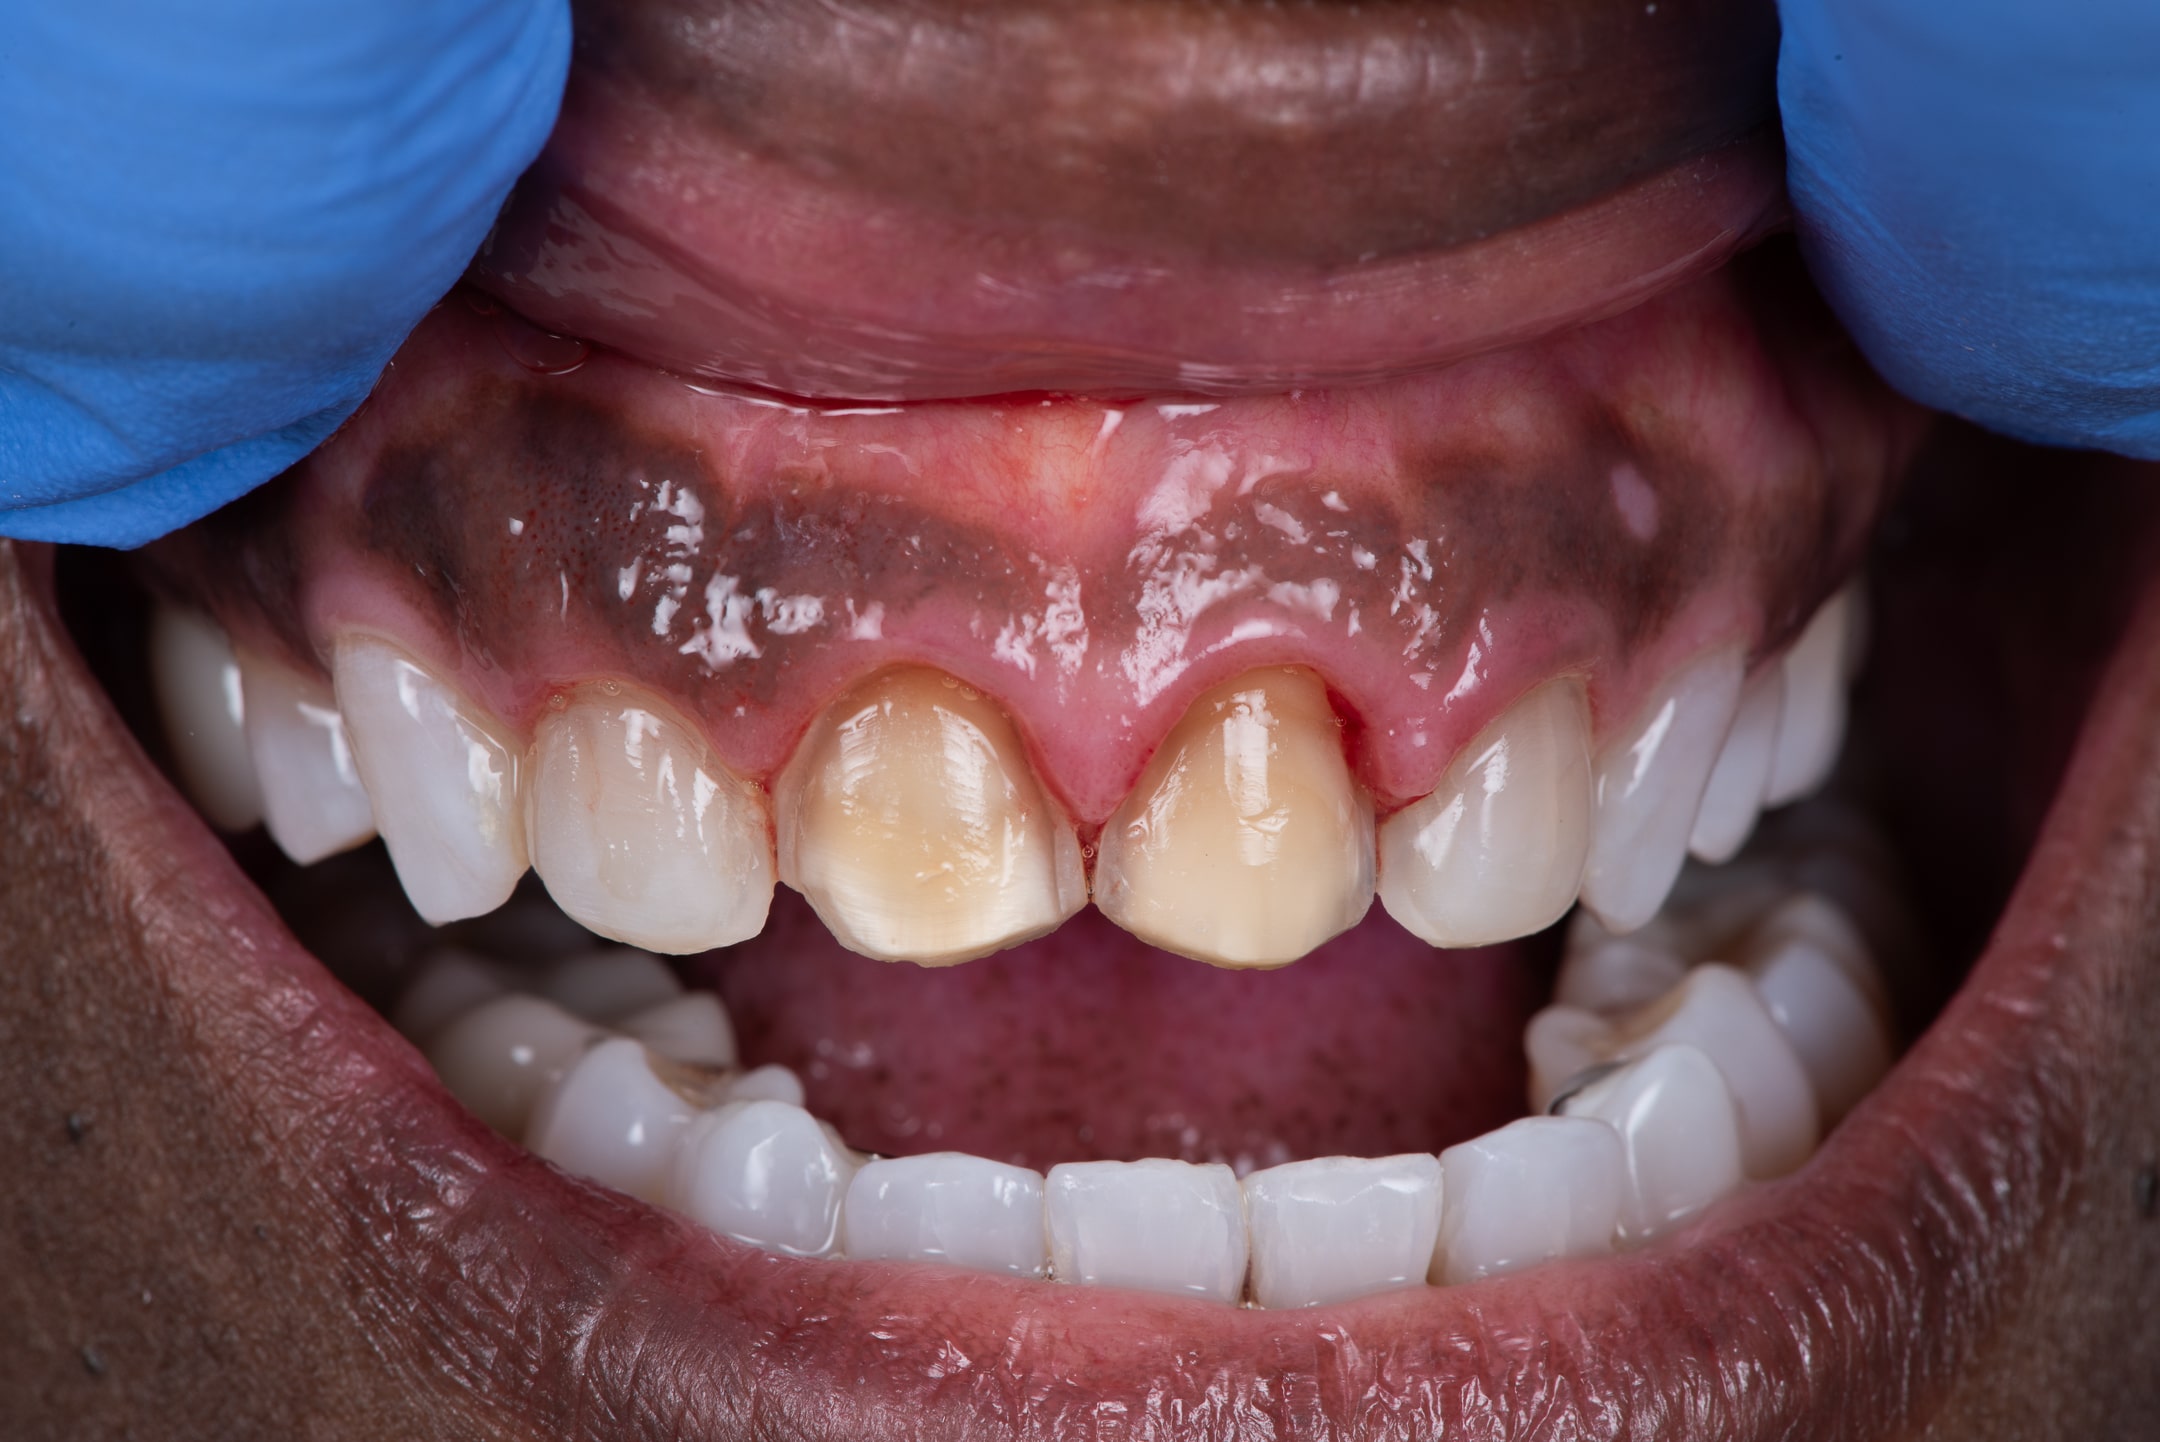

Step 3

When the remaining veneers were removed, we were able to see just how much tooth structure had been removed to place the initial veneers.

A shade was taken using special filters to ensure the ceramist has all the information they need to create life-like veneers.

As always, bonding under a rubber dam ensures the best possible bond of veneer to tooth.